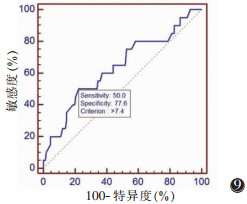

以敏感度为纵坐标,1-特异度为横坐标,分别绘制双侧SCM厚度差绝对值与SCM比率的ROC曲线,分别以双侧厚度差值≥0.74 cm和双侧厚度比率≥0.24为临界值,预测DDH的敏感度分别为50.0%和45.0%,特异度分别为77.6%和83.3%(图 9,10)。

| 图 9 SCM差值绝对值ROC曲线下面积为0.637,以双侧SCM厚度差值≥0.74 cm为临界值,测得敏感度和特异度分别为50.0%与77.6% |